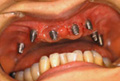

Q T-typeの特長を教えてください。 堤 従来のAQB1ピースを改良した形状で支台部にテーパー6°を付与しており、皮質骨と接するアバットメント部の径が約0.4 ?、通常サイズのものより太くなっています(左図) Q その改良の結果生まれたT-type固有の強みを教えてください。 堤 右表の3点がT-typeの特長でしょう。

堤 術式、ツールともに従来の1ピースと同様ですが、T-type専用のフィクサーが必要となります。 この点、営業担当者などに聞いていただき、手技を確実にして臨床に生かしていただきたいですね。